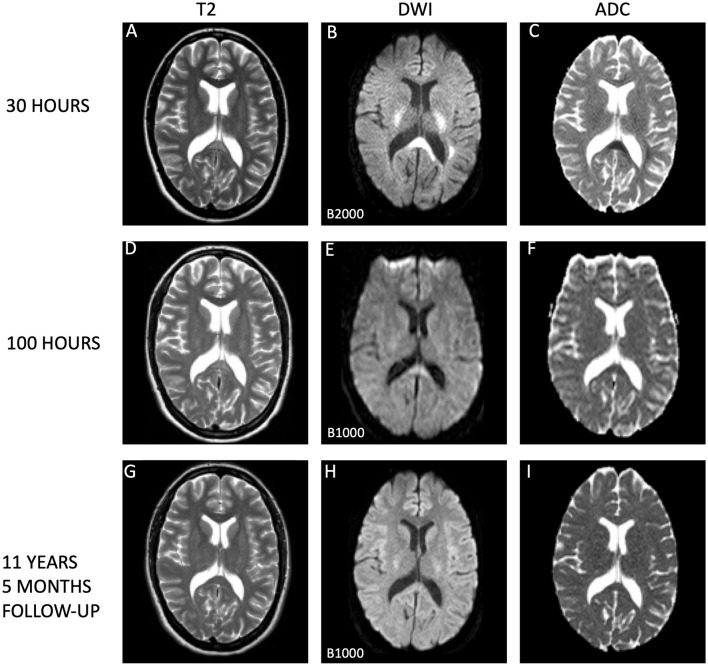

Cytotoxic lesions of the corpus callosum (CLOCC) are a clinicoradiological diagnosis, characterized by transient neurological symptoms and magnetic resonance imaging (MRI) changes in the splenium of the corpus callosum (SCC), which in most cases is completely reversible. However, the long-term pathophysiological trajectory and ultimate neurological outcomes of CLOCC remain largely unknown due to limited long-term follow-up data. We report an 11-year follow-up of a postpartum female with CLOCC, initially presenting with transient focal neurological symptoms and extensive diffusion-restricted white matter involvement including the SCC and surrounding area with diffusion restriction and low apparent diffusion coefficient values, indicative of cytotoxic edema. The edema regressed in days; over the years, she remained asymptomatic despite persistent white matter changes on MRI in the centrum semiovale. This case challenges the view of CLOCC as completely reversible and raises questions regarding the significance of lasting white matter changes. The enduring absence of neurological symptoms and stable radiological profile throughout the decade underscores the singular nature of CLOCC and the lasting, though isolated, impact on white matter. This report contributes a crucial perspective, suggesting that CLOCC may involve just an isolated episode without recurrent events or progressive neurological decline. By offering the first longitudinal analysis of a CLOCC episode with an extended follow-up of over a decade, our case enhances current knowledge about the long-term neurological and radiological landscape of this condition. It suggests a reevaluation of the conceptual understanding of CLOCC as an entirely reversible, non-relapsing disorder, highlighting the need for further research into its long-term impacts on cerebral white matter integrity.

胼胝体细胞毒性病变(CLOCC)是一种临床放射学诊断,其特征是短暂的神经系统症状和胼胝体(SCC)脾脏的磁共振成像(MRI)改变,在大多数情况下是完全可逆的。然而,由于长期随访数据有限,CLOCC的长期病理生理轨迹和最终神经学结局在很大程度上仍然未知。我们报告了一名产后CLOCC女性患者的11年随访,最初表现为短暂的局灶性神经症状和广泛的弥漫性白质受累,包括SCC和周围区域,弥漫性受限和低表观弥漫性系数值,表明细胞毒性水肿。水肿逐渐消退;多年来,尽管MRI显示半骨正中持续出现白质改变,但患者仍无症状。该病例挑战了CLOCC是完全可逆的观点,并提出了关于持久白质变化的重要性的问题。在整个十年中,神经系统症状的持续消失和稳定的放射学特征强调了CLOCC的独特性和对白质的持久影响,尽管是孤立的。该报告提供了一个至关重要的观点,表明CLOCC可能只是一个孤立的发作,没有复发事件或进行性神经功能衰退。通过首次对CLOCC发作进行纵向分析,并进行了超过十年的随访,本病例增强了当前对该疾病长期神经学和放射学的认识。该研究建议重新评估CLOCC作为一种完全可逆、非复发性疾病的概念理解,并强调需要进一步研究其对脑白质完整性的长期影响。